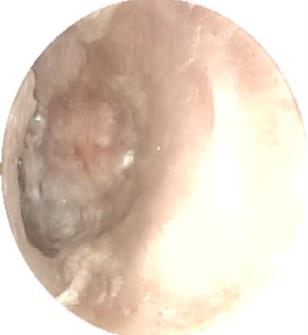

摘要:目的 探究一次性eyeMax洞察胰胆管成像系统辅助内镜逆行阑尾炎治疗术(ERAT)治疗阑尾炎的效果及安全性。方法 回顾性分析2023年4月-2024年9月在该院就诊,通过影像学或内镜检查确诊的54例非复杂性阑尾炎患者的临床资料。所有患者均行eyeMax洞察胆胰管成像系统辅助ERAT,于直视下观察阑尾腔,并通过冲洗、取石、扩张狭窄和支架引流等措施治疗阑尾炎。观察手术相关指标、术后疼痛程度、并发症发生情况、术后1年内复发率、结肠镜下表现、胰胆管成像系统下表现和胆胰管成像系统下治疗情况。结果 54例患者均顺利完成手术,技术成功率为100.0%,手术时间(60.6±27.9)min,住院时间(3.6±1.5)d;30例(55.6%)阑尾开口及周边黏膜充血水肿,2例(3.7%)可见脓液及污秽物流出;54例(100.0%)患者阑尾腔内壁充血水肿,51例(94.4%)可见腔内絮状物、脓液或脓苔附着,25例(46.3%)可见腔内粪石,15例(27.8%)可见管腔走形迂曲或狭窄。所有患者予以eyeMax洞察胰胆管成像系统治疗,简单灌洗54例,网篮取石20例,支架引流25例。术后VAS评分为0(0,0)分,明显低于术前的6(3,7)分,手术前后比较,差异有统计学意义(Z = -6.24,P = 0.000)。所有患者术后症状均暂时缓解,术中及术后未发生穿孔和大出血等严重不良事件。随访1年内,阑尾炎复发率为20.4%(11/54)。结论 EyeMax洞察胆胰管成像系统辅助ERAT是治疗非复杂性阑尾炎安全和有效的疗法,其具有直视下精准操作、保留阑尾功能、症状快速缓解、无X线暴露和精准诊疗阑尾病变等优势。值得应用于临床。